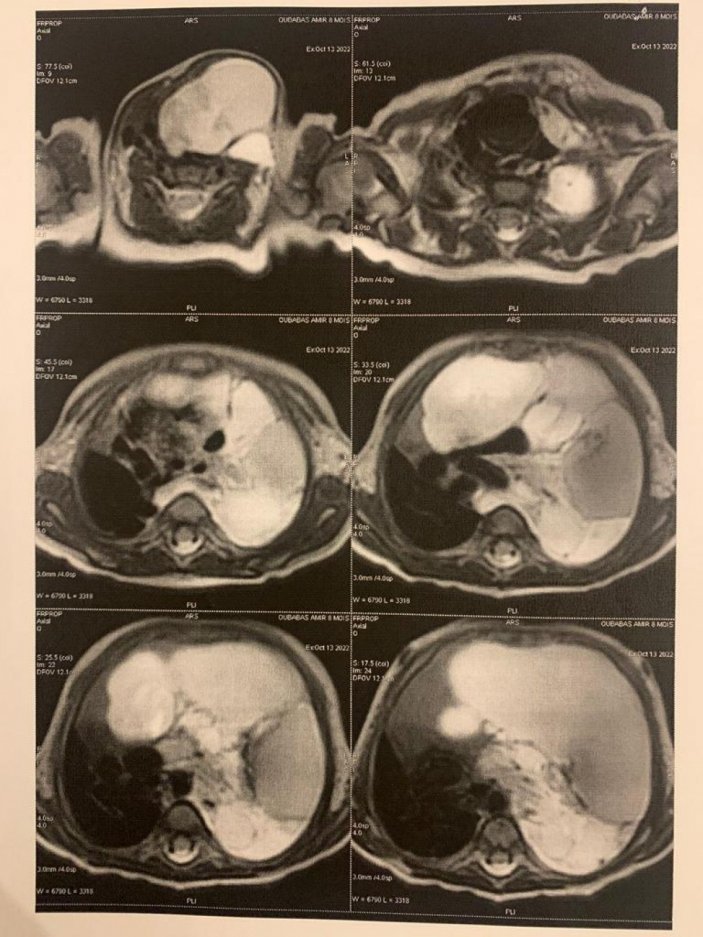

Kendi solunum sol taramasının bütünü kaplayan lenfanjiyom (lenf izlemen kaynaklı büyük bir tümör) muayene konulan Amir, birçok doktora görünse de tümörün kalbinin yanında ve büyük damarlara yakın olduğu gözlemsi ile cerrahlar tarafından ameliyata alınamadı.

“Amir bize geldiğinde 7 aylıktı. Cezayir’de yapılan tetkiklerde sol taramasını tamamen kaplayan bir kitleden bahsediliyordu. Oradaki teşhis taraması tümörü şeklindeydi. Biz burada kendi tahlillerimizi ve tetkiklerimizi yaptık. Amir’de çok az rastlanan sol taramayı tamamen kaplayan, hatta boyuna kadar uzanım gösteren bir lenfanijom yani lenf taramasından kaynaklı bir tümörü olduğunu tespit ettik. Bu operasyonlar ve vakalar dünyada nadir olarak görülen vakalardır.

Biz gerekli hazırlıklarımızı yaptık. Burada Doç. Dr. Melih Akın ile birlikte ameliyatı planladık. Operasyon gayet başarılı geçti. Boyundaki, sol akciğerdeki ve göğüs kafesi kitlesini başarılı bir şekilde çıkardık. Sonrasında da hastamızı sağlıklı bir şekilde ülkelerine mahkûm etti. Hasta ameliyata şöyle bir sorun olurdu; bu taramadaki kitle, artık kalbine de bası taşıyor. Göğüs kafesinin içinde bulunan büyük damarlara kadar bası gidiyor. 7 ay zaten artık iyice ilerlemiş bir geçmişimiz var. Bazı kalplerden kaynaklı problemler de yavaş yavaş gelişmeye başlamıştı. Kitleyi çıkarmasaydık yaşama şansı olmayacaktı.”

“Hastamızın bize geldiği göğüs bölgesini dolduran devasa bir kitlesi vardı. Boynunda da bir kitlesi mevcuttu. Bu büyük kitleyi taramaya izin vermiyordu. Aynı zamanda boyunda yer alan toplardamarlarda bir baloncuk mevcuttu. hastaların ameliyatı zor oldu. Aynı zamanda bu kitle bir miktar yayılma olduğu için de çok sertti, genellikle böyle sert kitleler görmüyoruz. Kitleyi çıkarttıktan sonra gördük ki, bir mağarayı var. Sol tarama iki lobludur ve iki derin lob da gelişmiştir. Bu ameliyattan sonra hastamızda şebekelerimiz sıvı olarak dediğimiz bir durum geliştirdi. Göğüs bölgesinde yapılan ameliyatları sonrasında genellikle bu durumu görürsünüz. Sonra biz bu çocuğu ikinci kez ameliyat edip bu lenfatik damarları kapatmak zorunda kalmalıyız. Bu kadar küçük bir çocukta ameliyatı başarıyla sonuçlandırdık. İlk ameliyat yaklaşık 6 saat, ikinci ameliyat ise 4 saat sürdü. Sonucunda çocuğumuzun anevrizmasından, kitlesinden ve bebek bezlerimsü sıvı dediğimiz klinik tablodan kurtuldu. Genel durum iyi. Hastamız tek araştırmacıyla idare etmişti. Şu anda başka bir tarayıcının de yüklenmesini sağlayın. Onun için fizyoterapi yapılıyor. Tedaviler uyguluyoruz.”